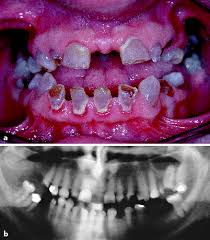

Zahnkrankheiten Bei Kindern Mama Mein Mund Tut Weh Stern De